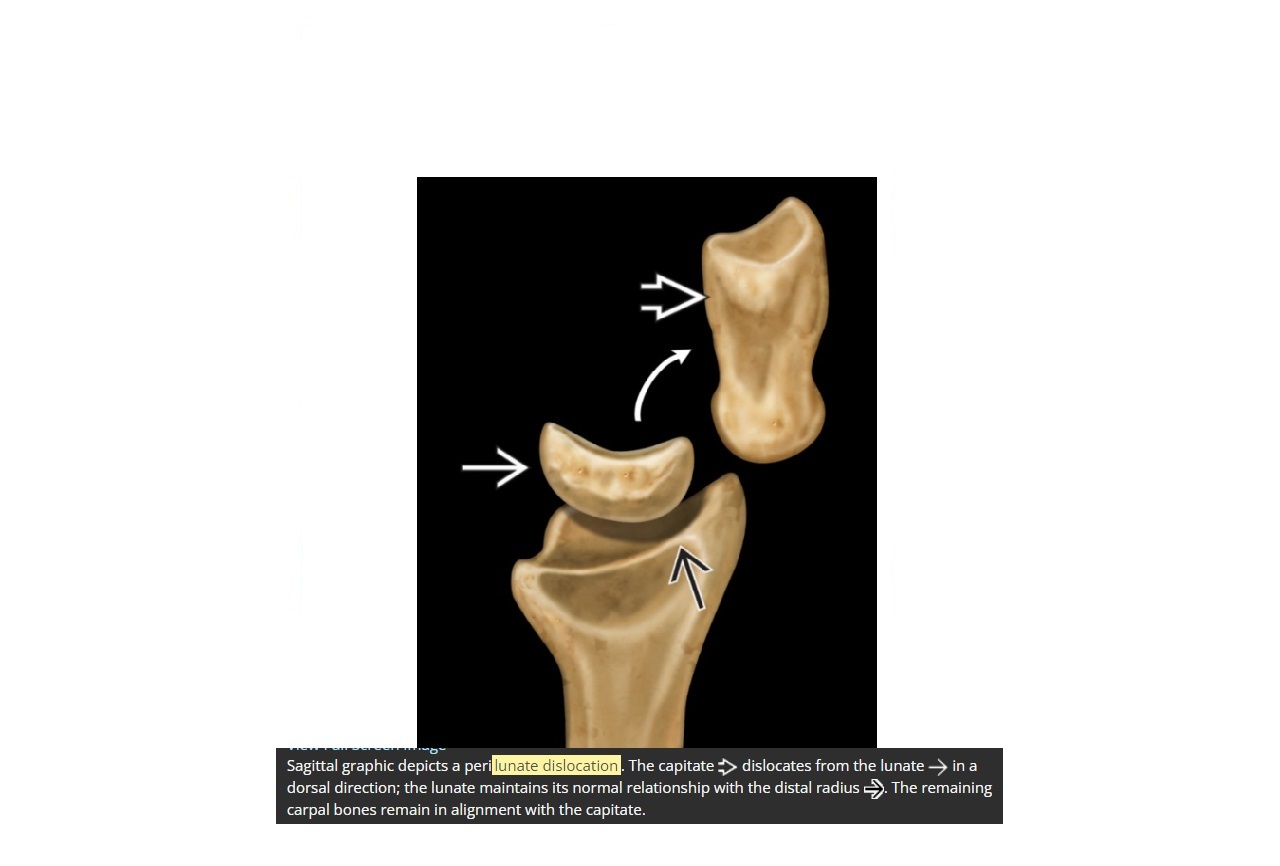

Which fracture is associated with a peri lunate dislocation?

Scaphoid (60%)

Capitate subluxes dorsally